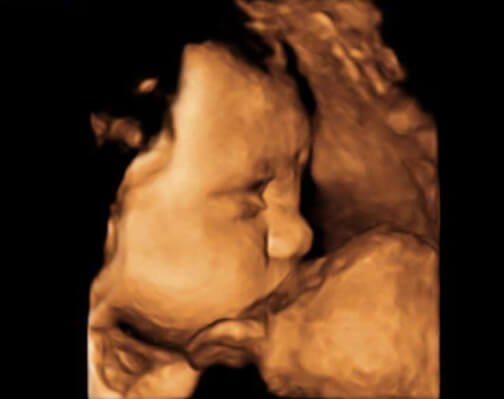

32 Haftalık Bebeğin Ultrason Görüntüsü

Öncelikle belirtmek isteriz ki bebeğinizin ultrason görüntüsünün internette bulduğunuz fotoğraflardan ya da başka annelerin görüntülerinden farklı olması gayet doğaldır ve bebeğinizde bir sorun olduğu anlamına gelmez; çünkü her bebeğin anne karnındaki duruşu ve hareketleri kendine özeldir.

• 32 haftalık bebeğinizin ultrason görüntüsünde, bebeğinizi baş aşağı dönmüş bulursanız hiç şaşırmayın; çünkü bebekler 32- 38. haftalar arasında doğum pozisyonu alırlar ve bebeklerin %60’ı bu pozisyonu 32. haftada alır.

• Eğer bebeğinizin henüz baş aşağı dönmemişse de endişelenmenize gerek yoktur; çünkü yukarıda da açıkladığımız gibi 38. haftaya kadar bebeğinizin vakti var ve o şimdilik en rahat ettiği pozisyonu tercih etmeye devam ediyor.

• 32 hafta gebelikte, bebeğinizi ultrasonda cenin pozisyonu almış olarak görmeniz de çok yüksek bir ihtimaldir.

• Eğer bebeğinizin ellerini yakından görecek kadar şanslıysanız, bu minnacık ellerin sizi çok şaşırtacağına eminiz. Peki bebeğinizin parmaklarının açık olduğunu ve henüz bükemediğini fark ettiniz mi?

32 hafta gebelik ultrason